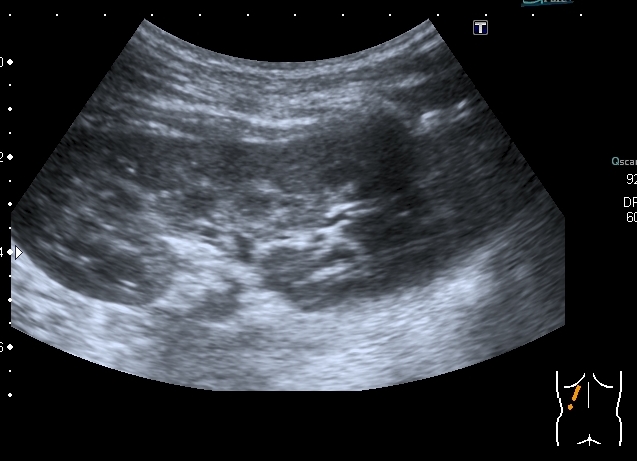

Мальчик 13 лет , страдает гемофилией А. Накануне ударился правым боком , появилась тёмная моча.

На УЗИ - такая картина:

Правая почка - паренхима не изменена, в срединном комплексе - лоханка с толстыми стенками и гиперэхогенным содержимым